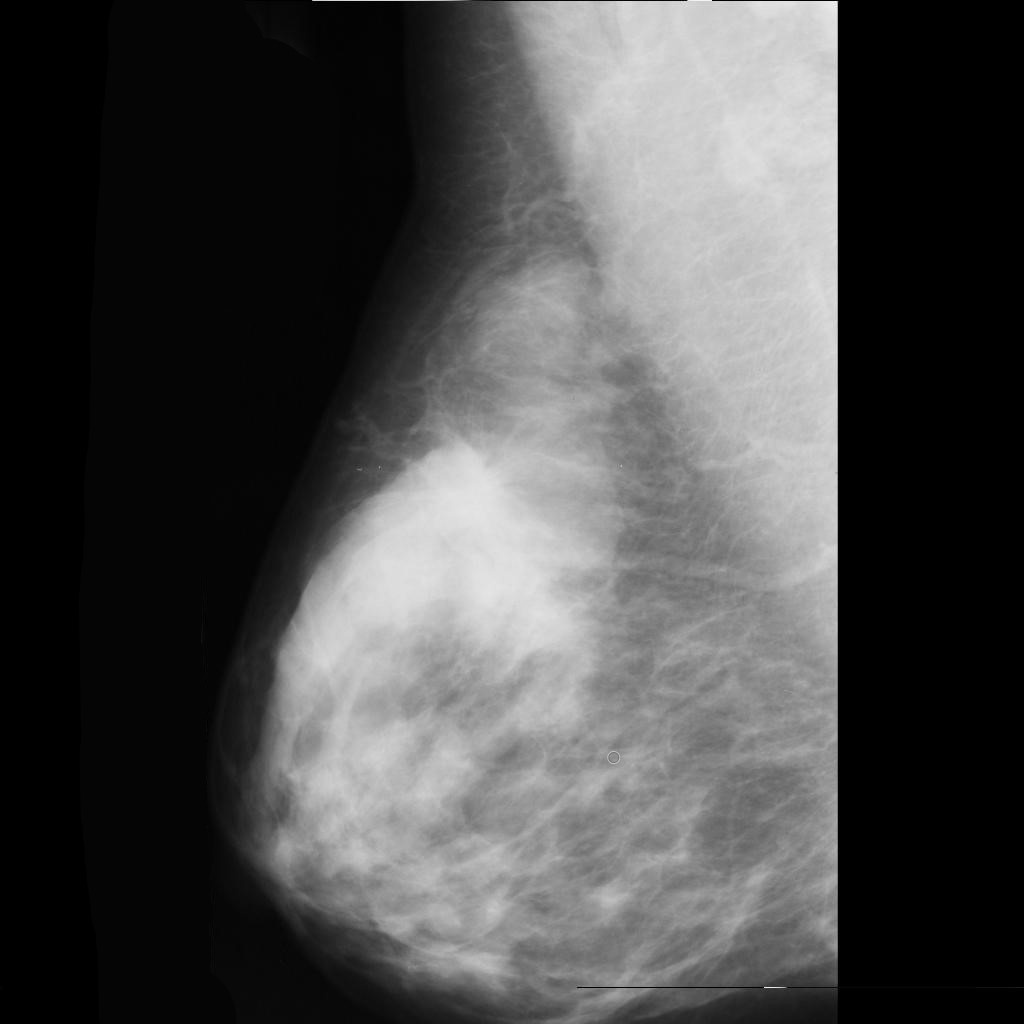

malignant